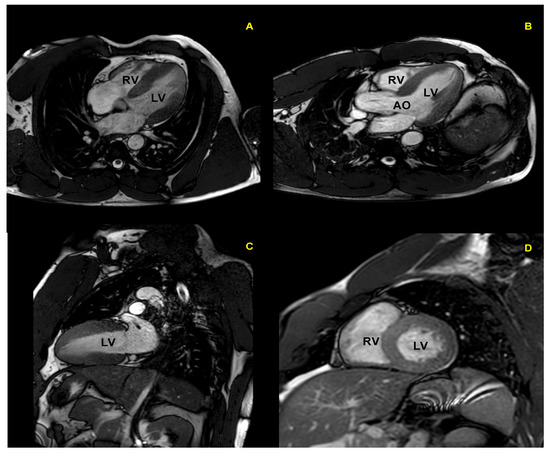

CMR is the gold standard for the definition of myocardial morphology, wall motion assessment, heart chambers size, and tissue characterization. It evaluates, with high accuracy and reproducibility, the heart chambers’ volume and mass, as well as global and regional contractile function [58,59,60]. It is the method of choice for the accurate evaluation of right ventricle morphology and function (Figure 4 and Figure 5).

Figure 5.

Cardiac magnetic resonance in a top-level power athlete (weightlifter). A significant harmonic and symmetric wall thickening is documented in 4-chamber (A), 5-chamber (B), 2-chamber (C), and short-axis (D) views. AO: aorta; LV: left ventricle; RV: right ventricle.